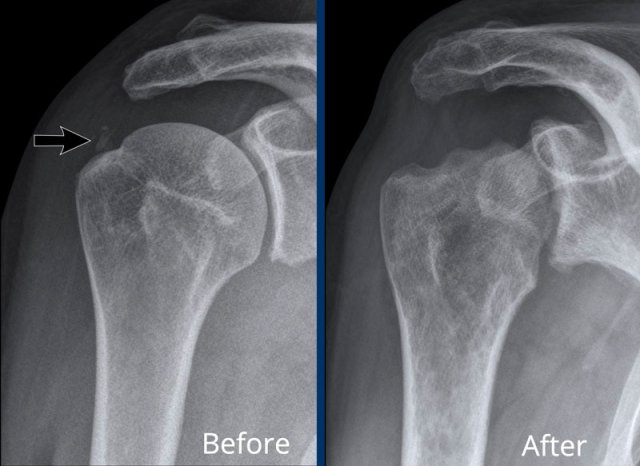

Images

A. Soft tissue calcifications in the rotator cuff. Patient got a subacromial injection for relief of symptoms.

B. After corticosteroid injection severe cartilage loss in the glenohumeral joint and bone destruction of the humeral head occured. This was the result of a septic arthritis, which is a rare complication of injection.